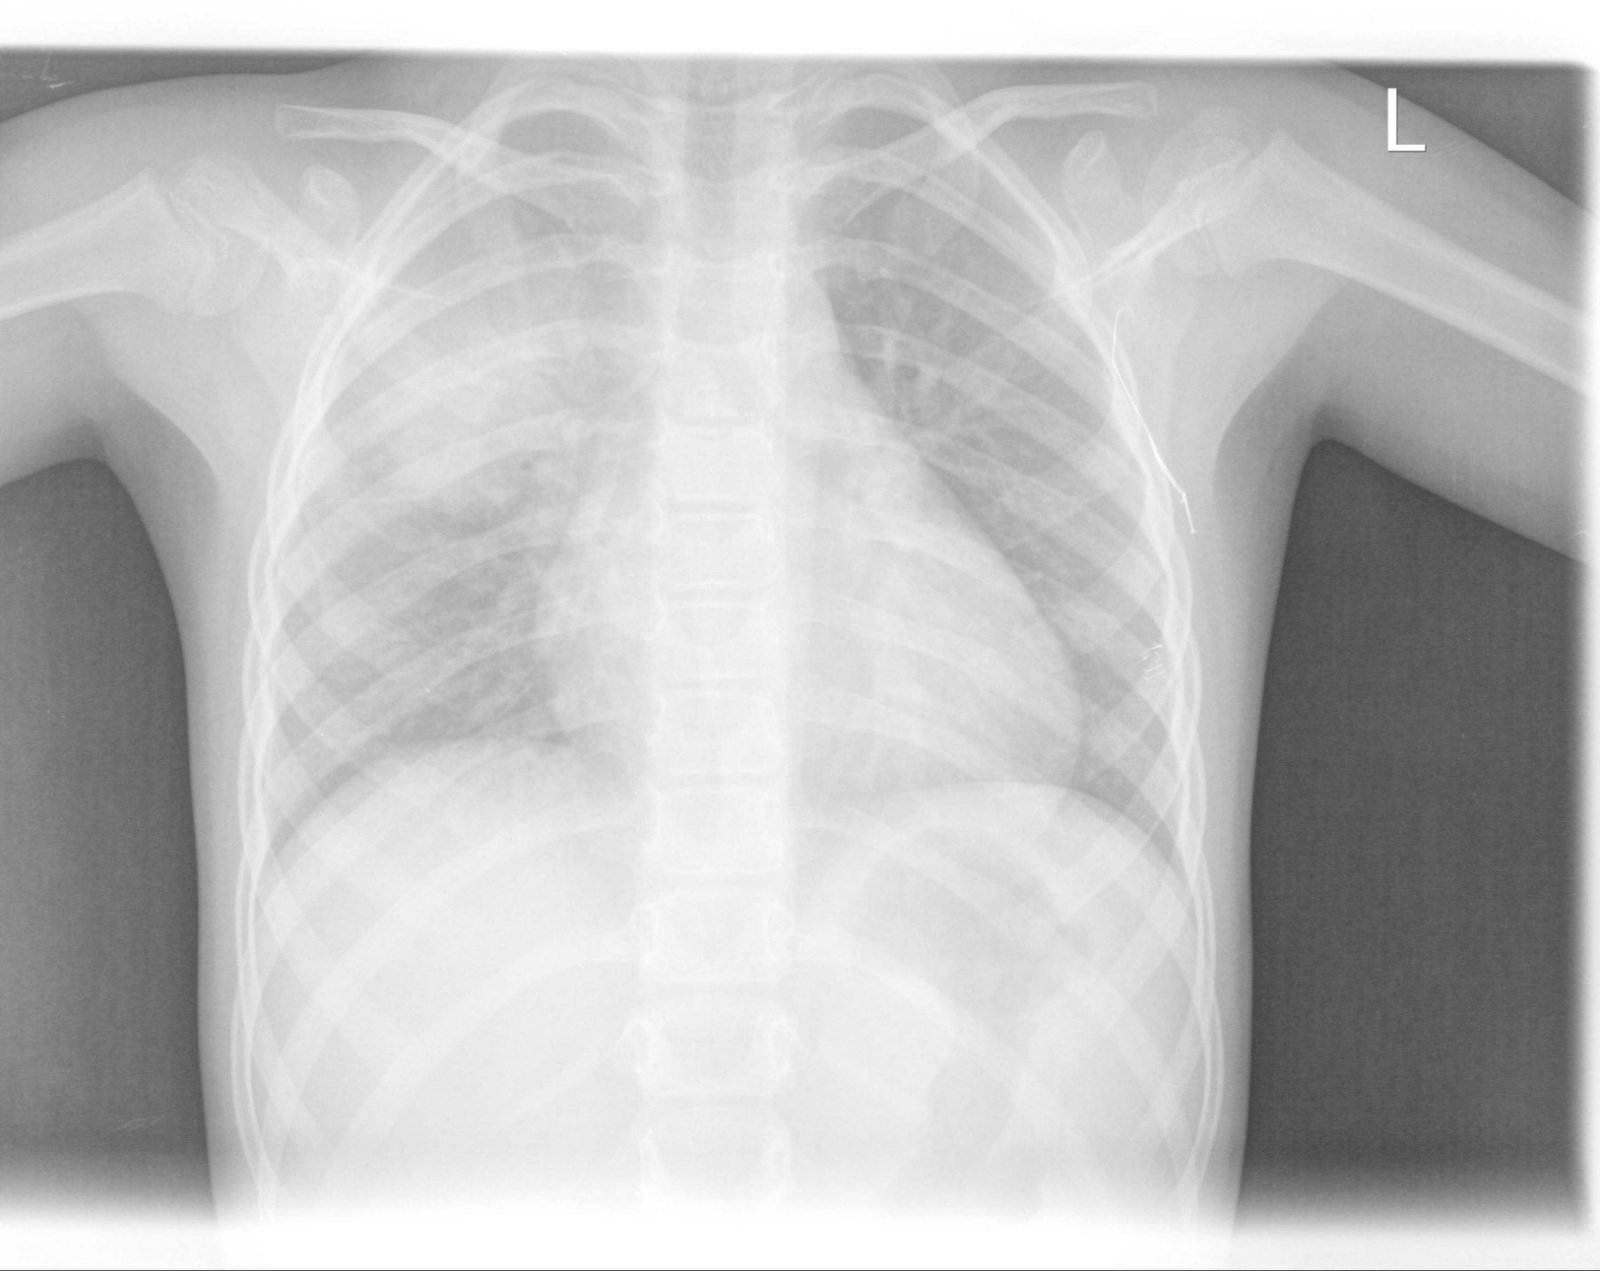

Детето започна с много висока температура около 40 градуса 3-4 дни,които почти не се повлияха от антипиретици и Хексалгин.Също и повръщане.След първият рентген ни назначиха два венозни антибиотика-7 дни-Медаксон и Амикацин ,инхалации с Пулмикорт ,Вентолин ,Урбазон и системи.Интересно беше ,че още след първата венозна апликация температурите изчезнаха.В болницата непрекъснато ни се натякваше ,че положението е много тежко,вероятно да се оправдае дългото лечение .Кръвните резултати -не бяха много добри.Суе-82 ,при изписването спадна